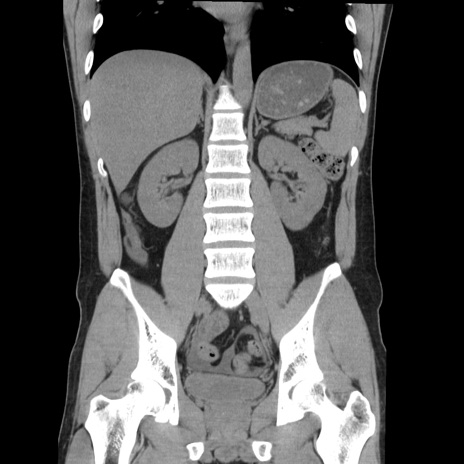

症例36(冠状断像)

【症例】20歳代 男性

【主訴】心窩部痛

【現病歴】今朝より上腹部痛あり。一旦軽快していたが再度出現したため救急要請。昨日夕に白身の魚を含む刺身を食べた。

【身体所見】BP 136/89mmHg、HR 74/min、BT 37.0℃、腹部:膨満、軟、心窩部に圧痛あり。反跳痛なし、筋性防御なし、腸雑音やや亢進あり。

【データ】WBC 17700、CRP 0.48